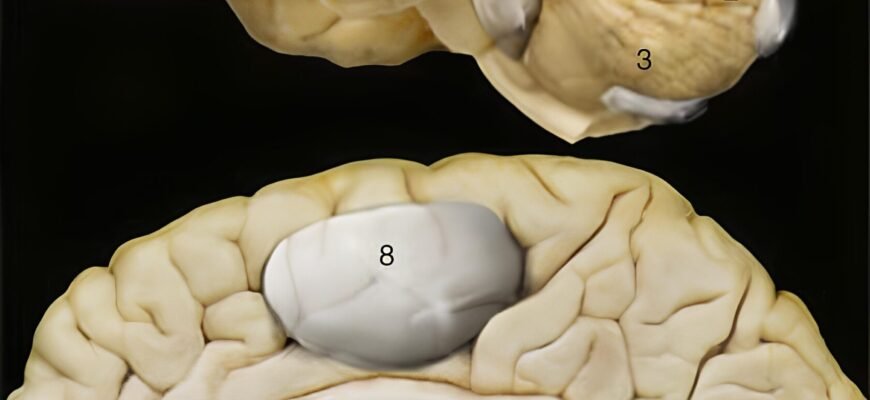

Що таке кіста головного мозку?

Уявіть себе у хащах інформаційного лісу, де кожне дерево — це факти, а галявини — знання. В цьому лісі кіста головного мозку — лише один із загадкових аспектів. Це порожнини, які можуть утворитися в будь-якій частині мозку. Вони можуть бути вродженими або набутими і зазвичай наповнені спинномозковою рідиною.

- Арахноїдальна кіста — розташована між поверхнею мозку і черепною коробкою.

- Ретенційна кіста — виникає внаслідок закриття протоків, що виводять рідину.

- Дермоїдна кіста — містить частинки тканин, як-от волосяні фолікули, жир.

- Епіфізарна кіста — утворюється в епіфізі, невеликій залозі в мозку.